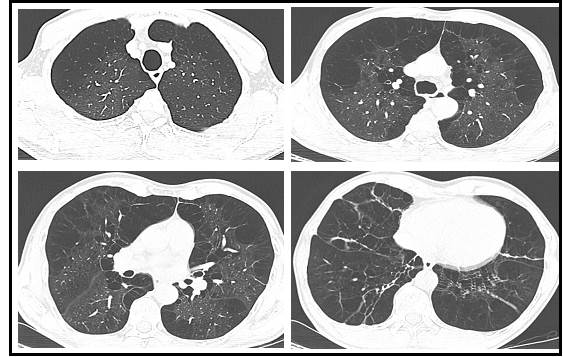

Aporta reportes de hemograma tipo IV con leucocitos 5.680/mm³, neutrófilos 53,3 %, linfocitos 29,1 %, eosinófilos 5,4 %, hemoglobina 16,8 g/dl, hematocrito 49,2 % y plaquetas de 246.000/mm³. La espirometría con broncodilatador muestra un índice de tiffeneau de 0,444, VEF1 (Volumen Espiratorio Forzado en un segundo): 58 % y la Capacidad Vital Forzada (CVF) del 106 % sin respuesta a broncodilatador. El ecocardiograma no revela alteraciones estructurales o de contractibilidad, con baja probabilidad de hipertensión pulmonar y una fracción de eyección preservada del 60 %. La tomografía de tórax sugiere hallazgos de enfisema centroacinar, paraseptal y paraacinar de predominio en bases, asociado a un aumento del volumen pulmonar (ver Figura 1).

Dentro los hallazgos reportados por tomografía, también se han descrito divergencia en las anormalidades enfisematosas entre individuos homocigotos PI*ZZ y PI*SZ, siendo más prominente el compromiso basal y en los vértices en el primero, 64% y 36 % respectivamente. A diferencia los individuos PI*SZ, 42,9 % tienen enfisema dominante en la zona superior 23,24.